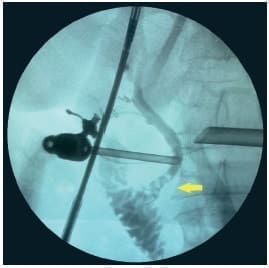

Con estos datos, se llevó el paciente a cirugía para colecistectomía laparoscópica y colangiografía intraoperatoria, en la que se identificó coledocolitiasis múltiple (Figura 2).

Figura 2. Colangiografia intraoperatoria donde se aprecian varios defectos de llenamiento

(flecha) correspondientes a calculos – Sospecha de Coledocolitiasis